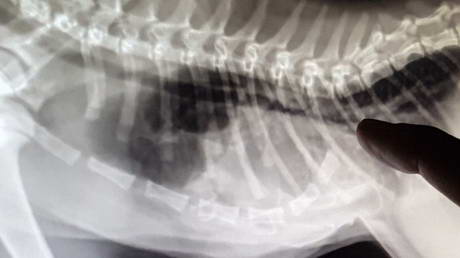

This is a myelogram

Play this video

26 Feb 2017

(Duration 01:57)